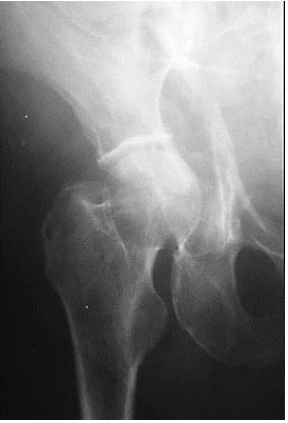

A imagem abaixo mostra: